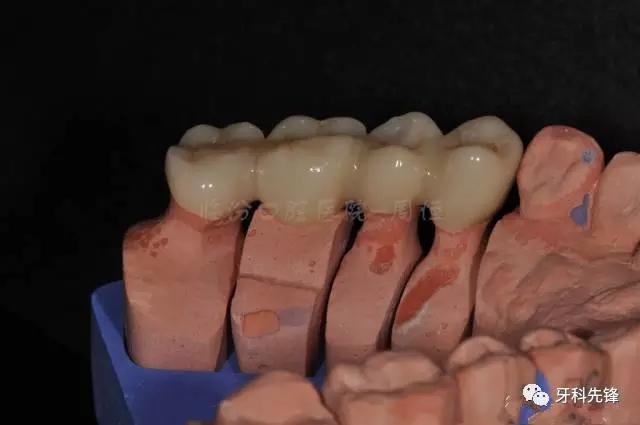

圖13牙體預備模型照

640.webp (17).jpg